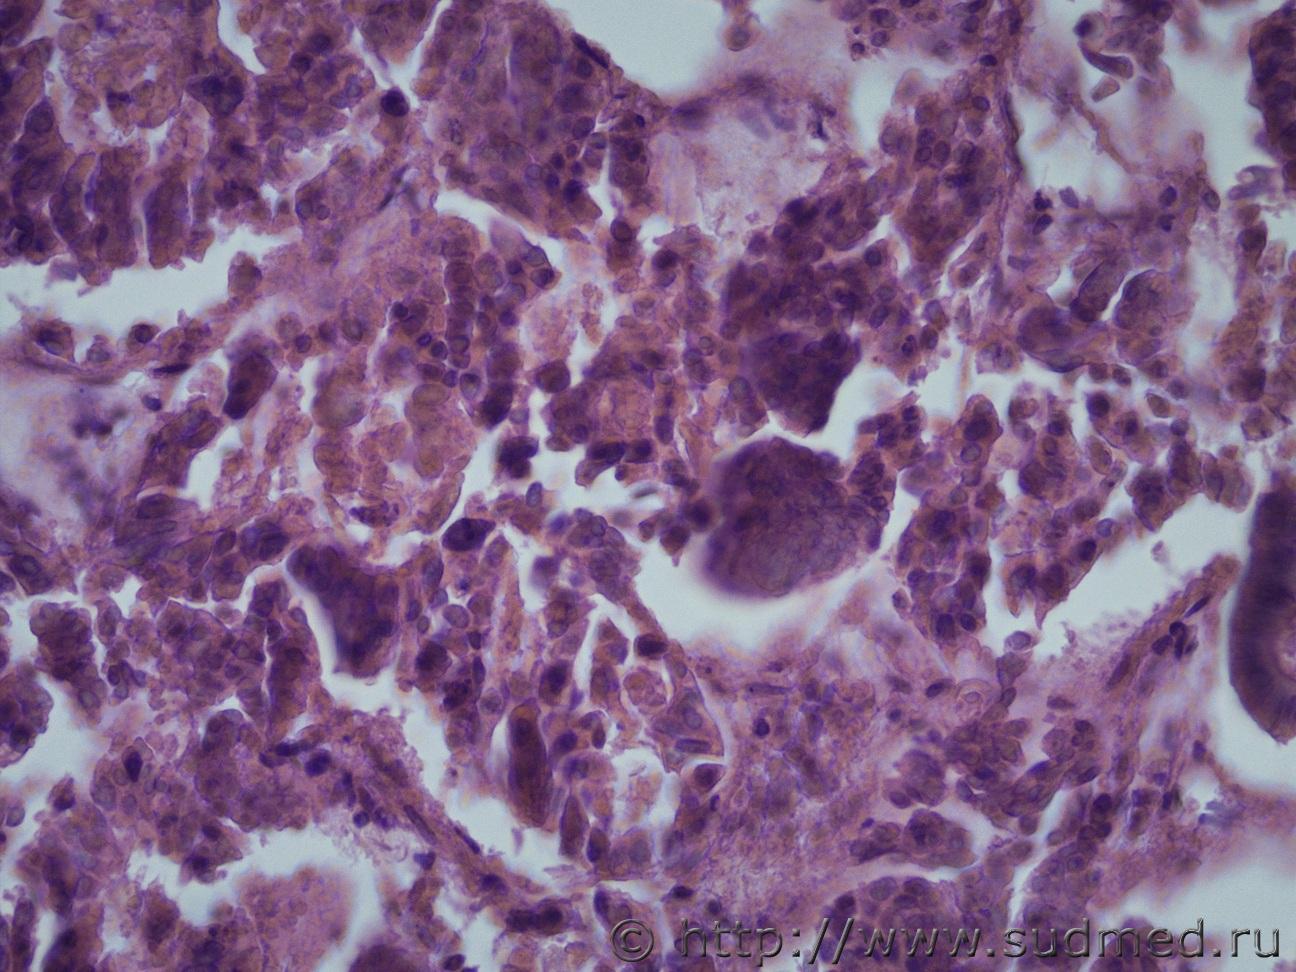

опухоль печени |

IVANNES опухоль печени 21.11.2018 - 10:39

Anton Эпителий желчного типа, д.б. холангиокарцинома. 21.11.2018 - 14:02

andy_bob Железистая ткань с фигурами патологического митоза... 29.11.2018 - 12:39![]() ![]() |